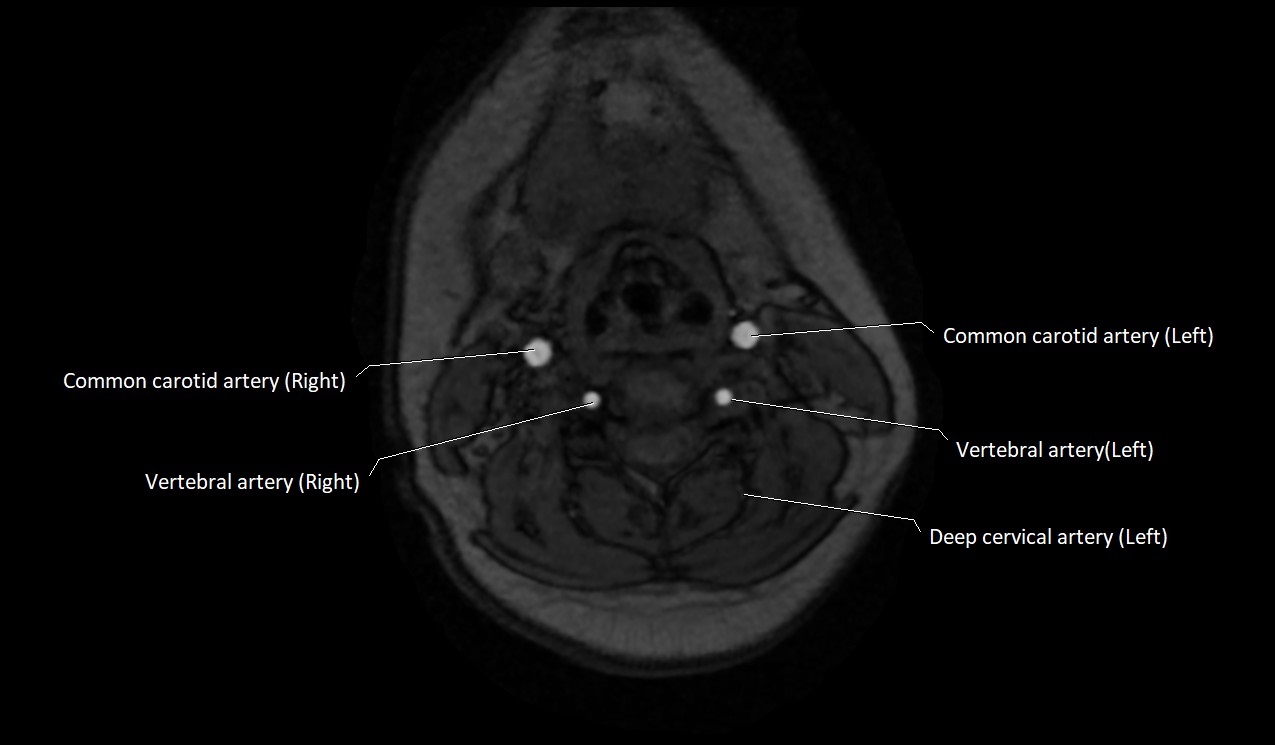

MRI images

image